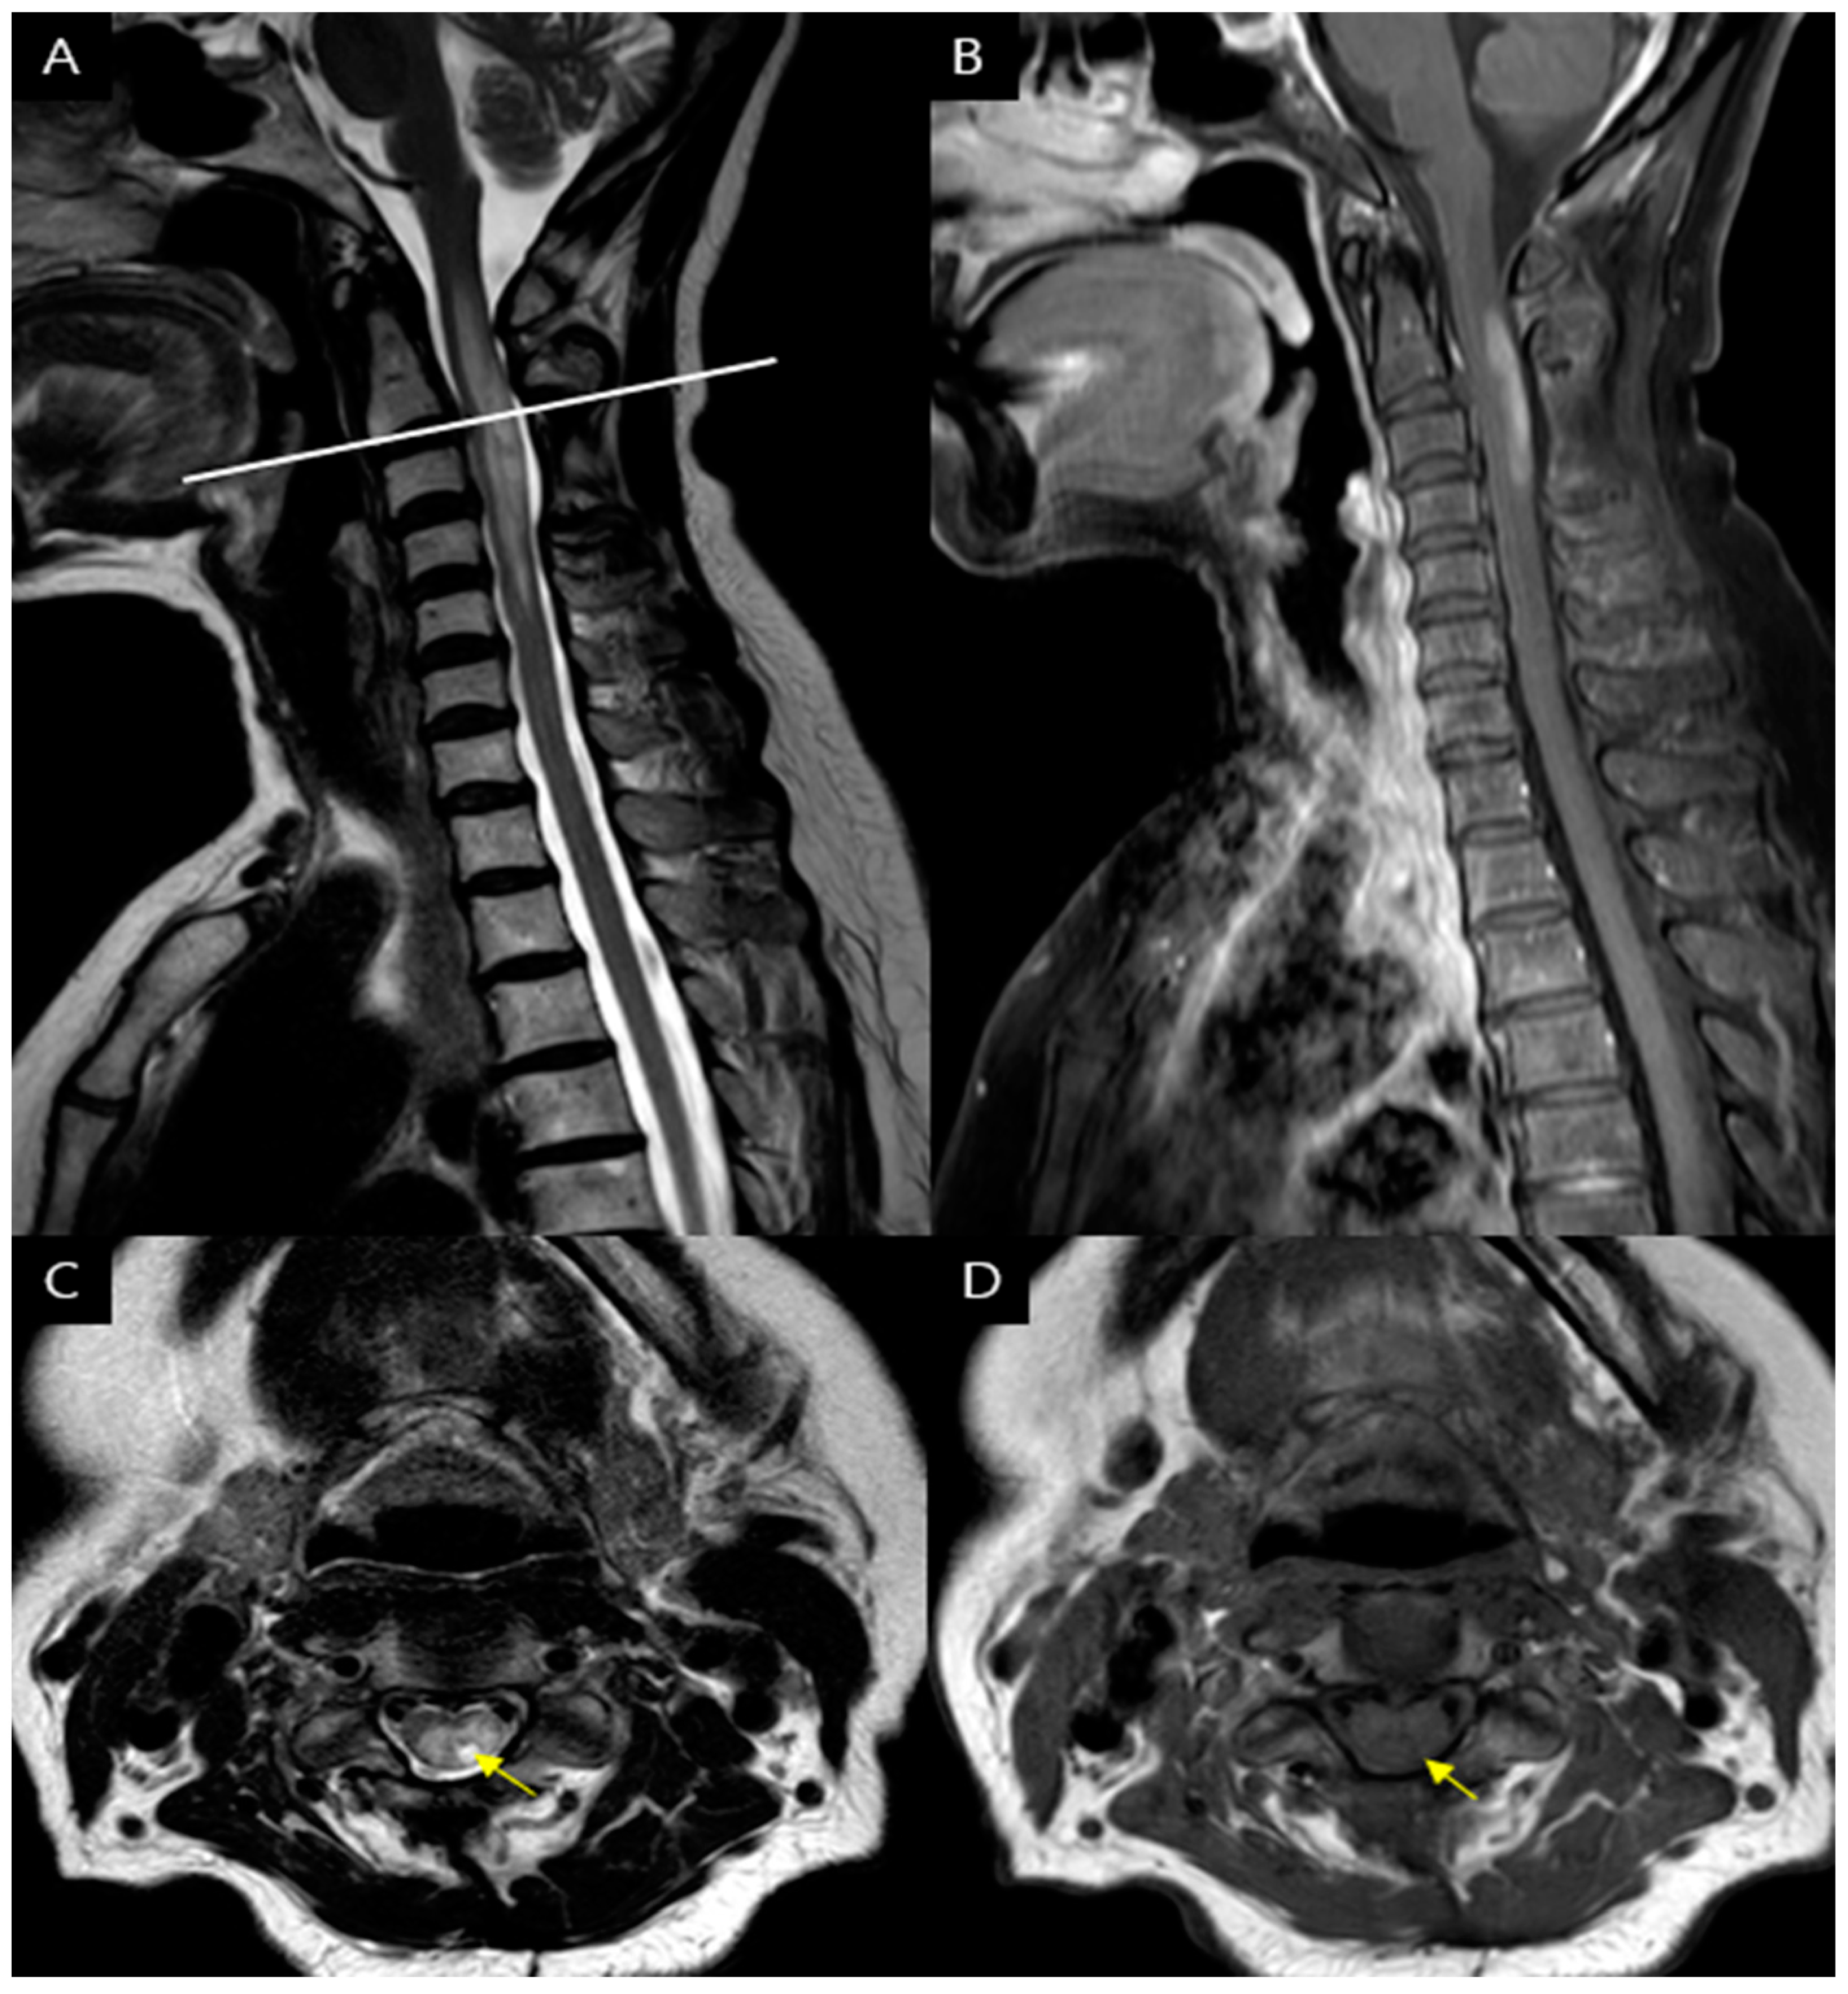

A 66-year-old female patient with a history of hyperlipidemia presented to the hospital three years ago with posterior neck pain, radiating pain on left arm and left upper limb motor weakness. The patient presented with left-sided motor weakness: manual muscle testing (MMT) score of 4 that is nearly normal, and reflexes were intact. The patient also complained of tingling and numbness in the left upper limb, with a Numeric Rating Scale (NRS) score of 3. However, the patient didn't complain of any visual symptoms. At that time, a cervical spine MRI revealed a herniated disc at the C2-3 level, the increased signal intensity of the spinal cord at the C3 to 4 levels (Figure 1). Based on the patient's motor weakness, radiating pain, and MRI findings, she was diagnosed with cervical spondylotic myelopathy and underwent C2-3-4 posterior decompression during hospitalization. Following the surgery, the patient showed improvement in left limb motor weakness and radiating pain and was followed up as an outpatient.

The initial C-spine MRI revealed disc herniation with cord compression at the C2-3 . In cases of cord compression caused by disc herniation, it is common to observe spinal cord signal changes primarily in proximity to the site of compression.[5] However, in this case, despite the compression being located at C2-3, there were signal intensity change observed at C3-4, suggesting that the observed signal alteration may not be solely attributable to compression. While autoimmune diseases are commonly observed in individuals in their 50s, they have also been reported to occur in individuals in their 90s.[6] Considering that spondylosis represents a degenerative change associated with aging, it is reasonable to assume that the likelihood of developing disc herniation or spondylotic myelopathy increases, especially in older individuals.[7] It is crucial to be aware of the potential occurrence of transverse myelitis in elderly patients with spondylosis. Therefore, when the spinal cord MRI findings do not align with the degenerative structural changes typically associated with spondylosis, it is essential to consider alternative differential diagnoses apart from spondylotic myelopathy.

Furthermore, at the C4-5 level, where no cord compression was observed, there is a high signal change within the spinal cord that appears brighter than the cerebrospinal fluid signal. These findings correspond to bright spotty lesions (BSLs), which are defined as hyperintense intramedullary lesions on axial T2-weighted images usually associated with T1 low signal. BSLs are considered a characteristic feature of NMOSD, distinguishing it from conditions such as multiple sclerosis (MS) and other disorder that revealed LETM. [5,8] if BSLs do not correlate with the level of compression, additional investigations should be conducted to consider the possibility of NMOSD.

Figure 1. Spine magnetic resonance imaging findings on first hospitalization. (A) The T2-weighted sagittal image reveals the increased spinal cord signal intensity at the C3 to 4 levels. (B, C) There was a herniated disc at the C2-3 levels (a) with high signal intensity on T2 weighted image and iso signal intensity on T1 weighted image (yellow arrow). (D) The T2-weighted axial image reveals a hyperintense lesion at the C4-5 level (b). The lesion appears brighter than the surrounding CSF, indicating the presence of bright spotty lesions (BLSs) (E) T1-weighted image reveals partially hypointense but not as low as the surrounding CSF or isointense. (yellow arrowheads).